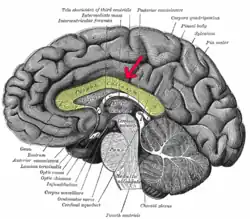

Tálamo

El tálamo está situado por encima del tronco del encéfalo, casi en el centro del cerebro. Mide alrededor de 3 cm de largo y está formado por materia gris es decir el soma de células neuronales. Cumple la función de estación de relevo de las señales nerviosas y centro de integración donde se procesan los impulsos sensoriales antes de continuar su recorrido hasta la corteza cerebral. También recibe señales que siguen la dirección opuesta y llegan al tálamo procedente de la corteza cerebral.[28]

Hipotálamo

El hipotálamo es una pequeña región del cerebro formada por sustancia gris. Está situado inmediatamente debajo del tálamo. Tiene el tamaño aproximado de una almendra y desempeña importantes funciones, entre ellas enlazar el sistema nervioso con el sistema endocrino a través de la hipófisis.[28]

Cuerpo calloso

El cuerpo calloso es una importante estructura del cerebro que está formada por fibras que actúan como vía de comunicación entre el hemisferio cerebral derecho y el izquierdo, con la finalidad de que ambos funcionen de forma conjunta y complementaria.[30]

Cápsula interna

La cápsula interna es un grueso conjunto de fibras nerviosas tanto ascendentes como descendentes que comunican la corteza con las regiones inferiores del sistema nervioso central, las fibras son de origen diverso, pero muchas de ellas transportan información motora o sensitiva. En su trayecto pasan cerca de la región del tálamo y los ganglios basales. La cápsula interna es una región muy sensible, cualquier lesión en esta zona daña numerosas fibras nerviosas y provoca en consecuencia déficits neurológicos graves.[28]